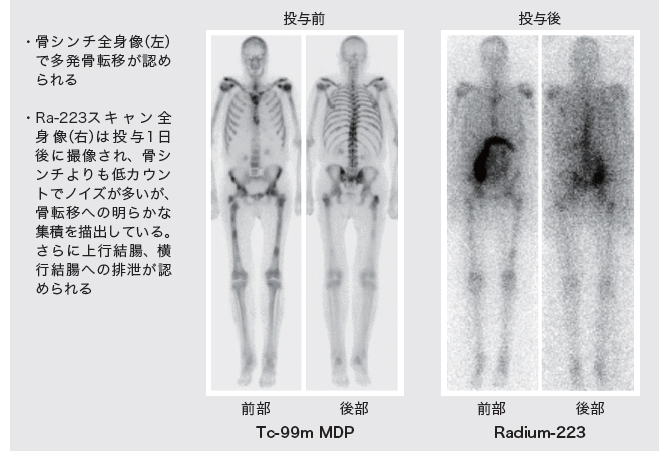

ラジウム製剤 前立腺がん骨転移に期待 医療ニュース Medical Tribune

第15回日本核医学会春季大会ランチョンセミナー 骨転移の診断 治療